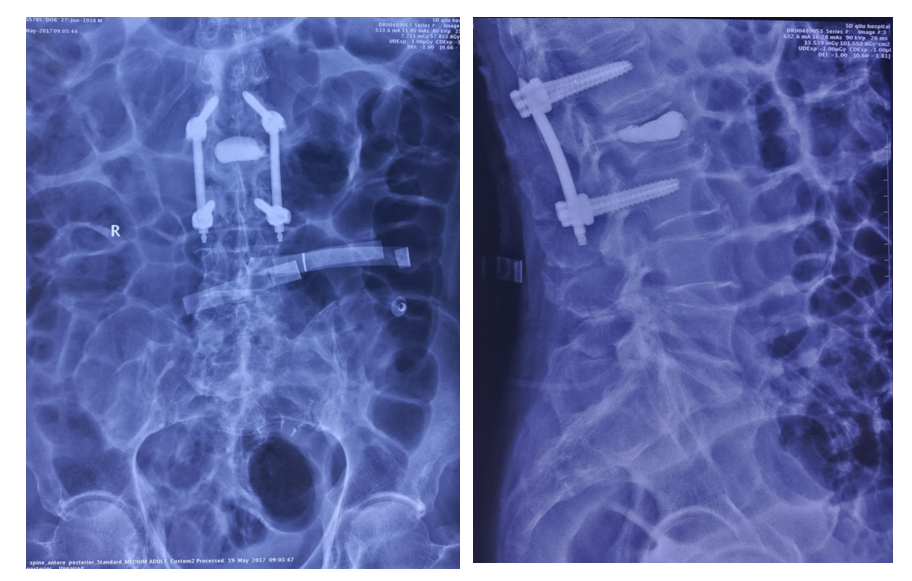

术后影像学

术后刀口

术后检查

手术治疗:T10-T12棘突椎板切除;T11 截骨后凸矫形;T9-L1椎弓根固定,均为骨水泥螺钉,安放横联两根;T10/11及各椎板后方大量植异体骨及自体骨。

术中透视

术后X线